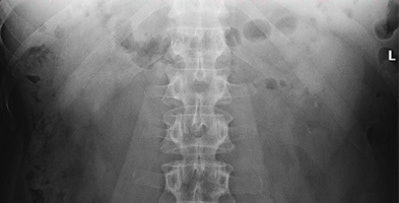

![]() |

| Two lithiasis in left kidney, seen on both techniques but much clearer on the tomosynthesis image (above), as well as nice visualization of the contour of the kidney. Images courtesy of Dr. Koen Mermuys. |